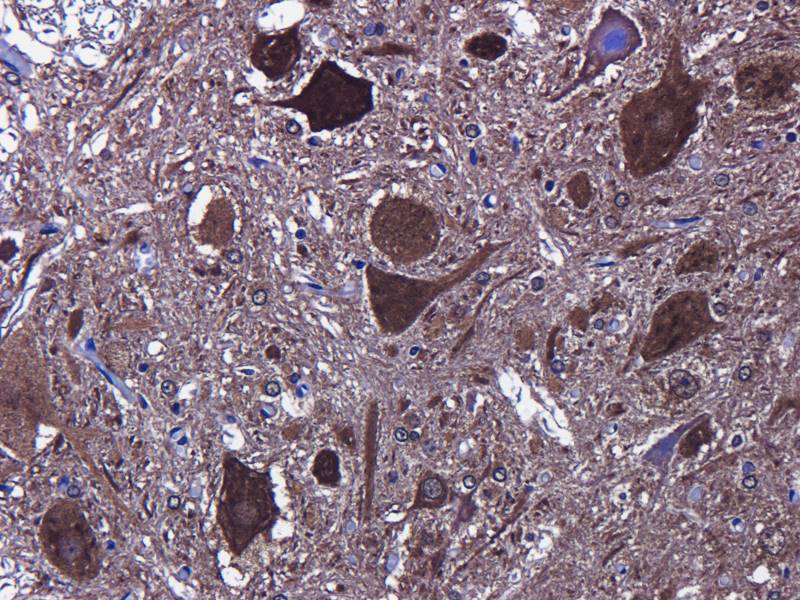

IHC staining of FFPE human brain with Ubiquitin antibody (clone PBQN-1). Required HIER: boil tissue sections in pH9 10mM Tris with 1mM EDTA for 10-20 min followed by cooling at RT for 20 min.